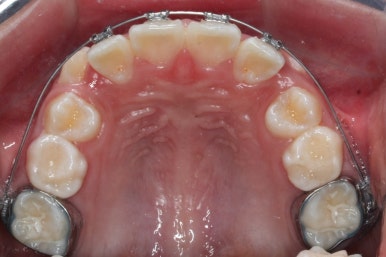

영구치도 이제 거의 다 나왔고 삐뚤한 다른 부분도 전체 메탈장치를 붙였습니다.

장치는 윗니부터 붙였습니다.

입안에 장치가 있다보니 불편할 수 있는데요. 이물감을 최소화 하고자 이동을 해야 할 양이 적은 아랫니들은 천천히 장치를 붙이기로 했습니다.

아래쪽에도 이제 장치를 전부 부착했습니다.

한 쪽의 송곳니는 제위치로 벌써 자리를 잡았네요.